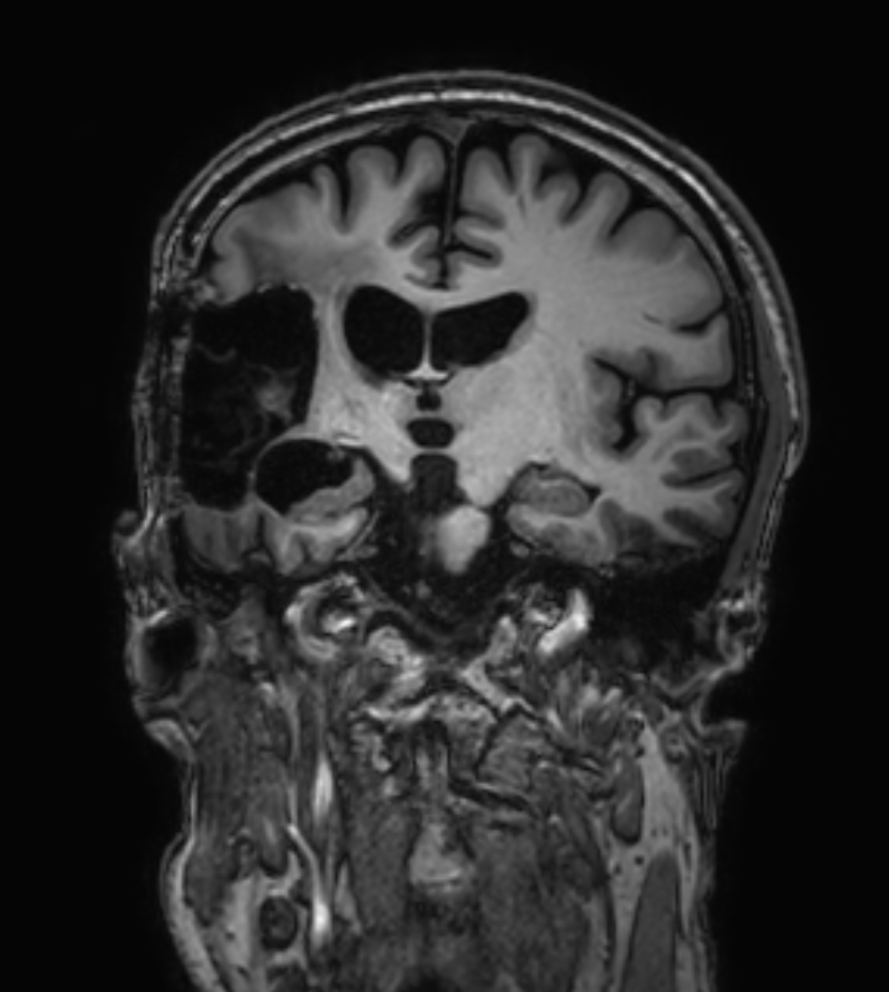

3D FLAIR - Coronal reformat

3D T1w TFE - Coronal reformat (with gado)

3D T1w TFE - Coronal reformat (high res, with gado)